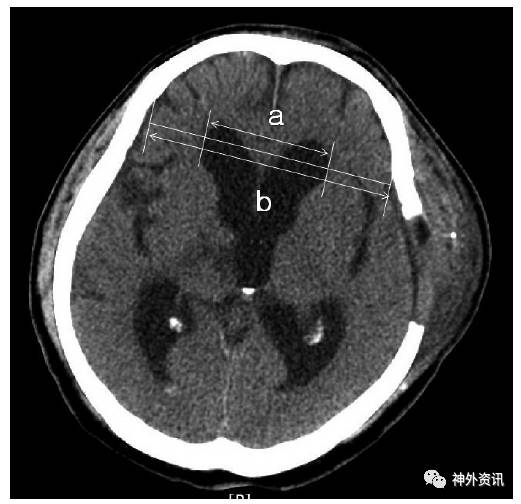

图1. 脑水肿定义为改良前角指数a/b≥33%。